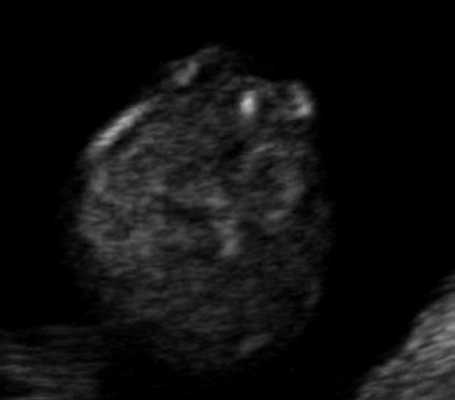

Самый тяжелый и инвалидизирующий порок в области задней черепной ямки - аномалия Денди-Уокера, характеризующаяся наличием кистозного образования в области большой цистерны с аплазией червя мозжечка. Наш опыт показывает, что в I триместре в срок 12 недель при осмотре аксиального среза головы плода можно визуализировать кистозное образование в области задней черепной ямки, однако провести дифференциальный диагноз между различными патологиями этой области, имеющими разный прогноз, по этому скану невозможно (рис. 9).

Рис. 9. Аксиальный срез головы плода, киста задней черепной ямки, беременность 12 недель.